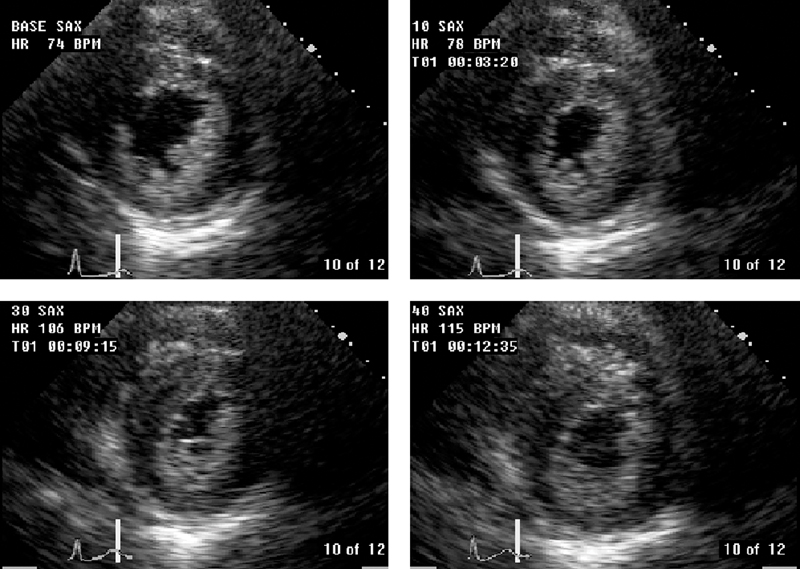

فحوصات تشخيصية لبعض امراض القلب والشرايين التاجية